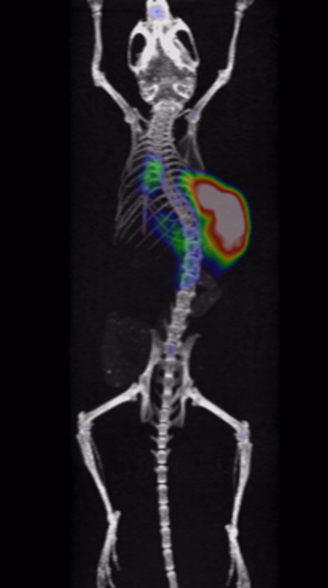

It has been proved that Cu-64-marked nanoantibodies are well-targeting for tumors, with high local uptake and long retention